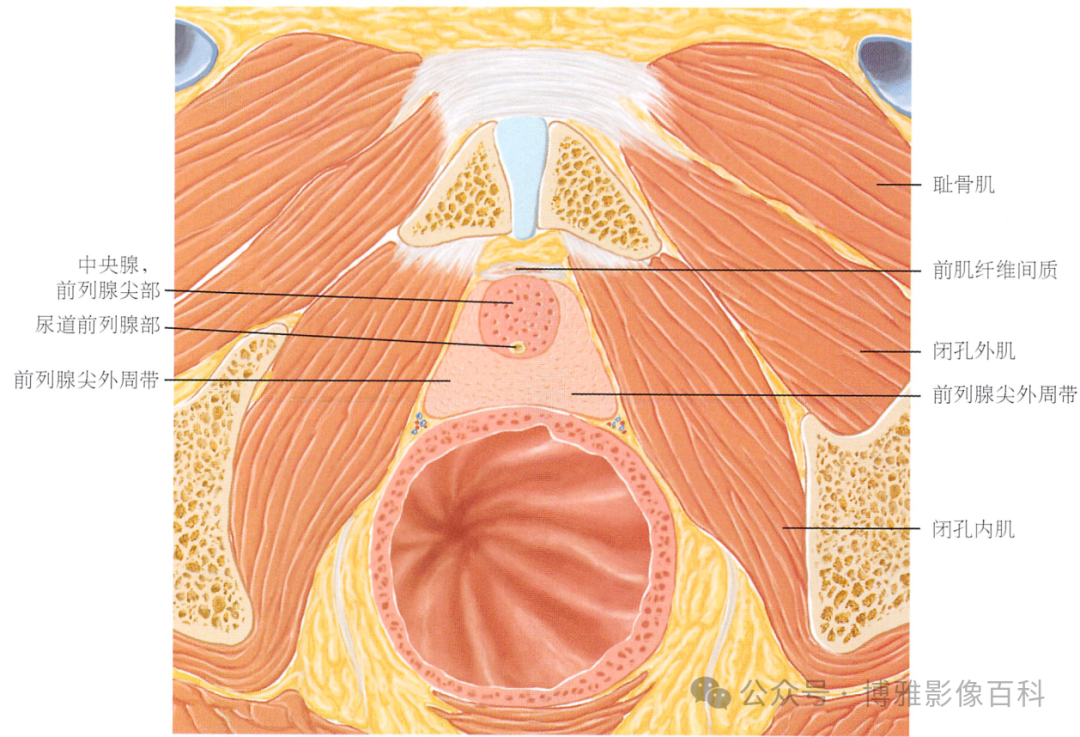

解剖学

前列腺分区解剖学

MR 解剖学